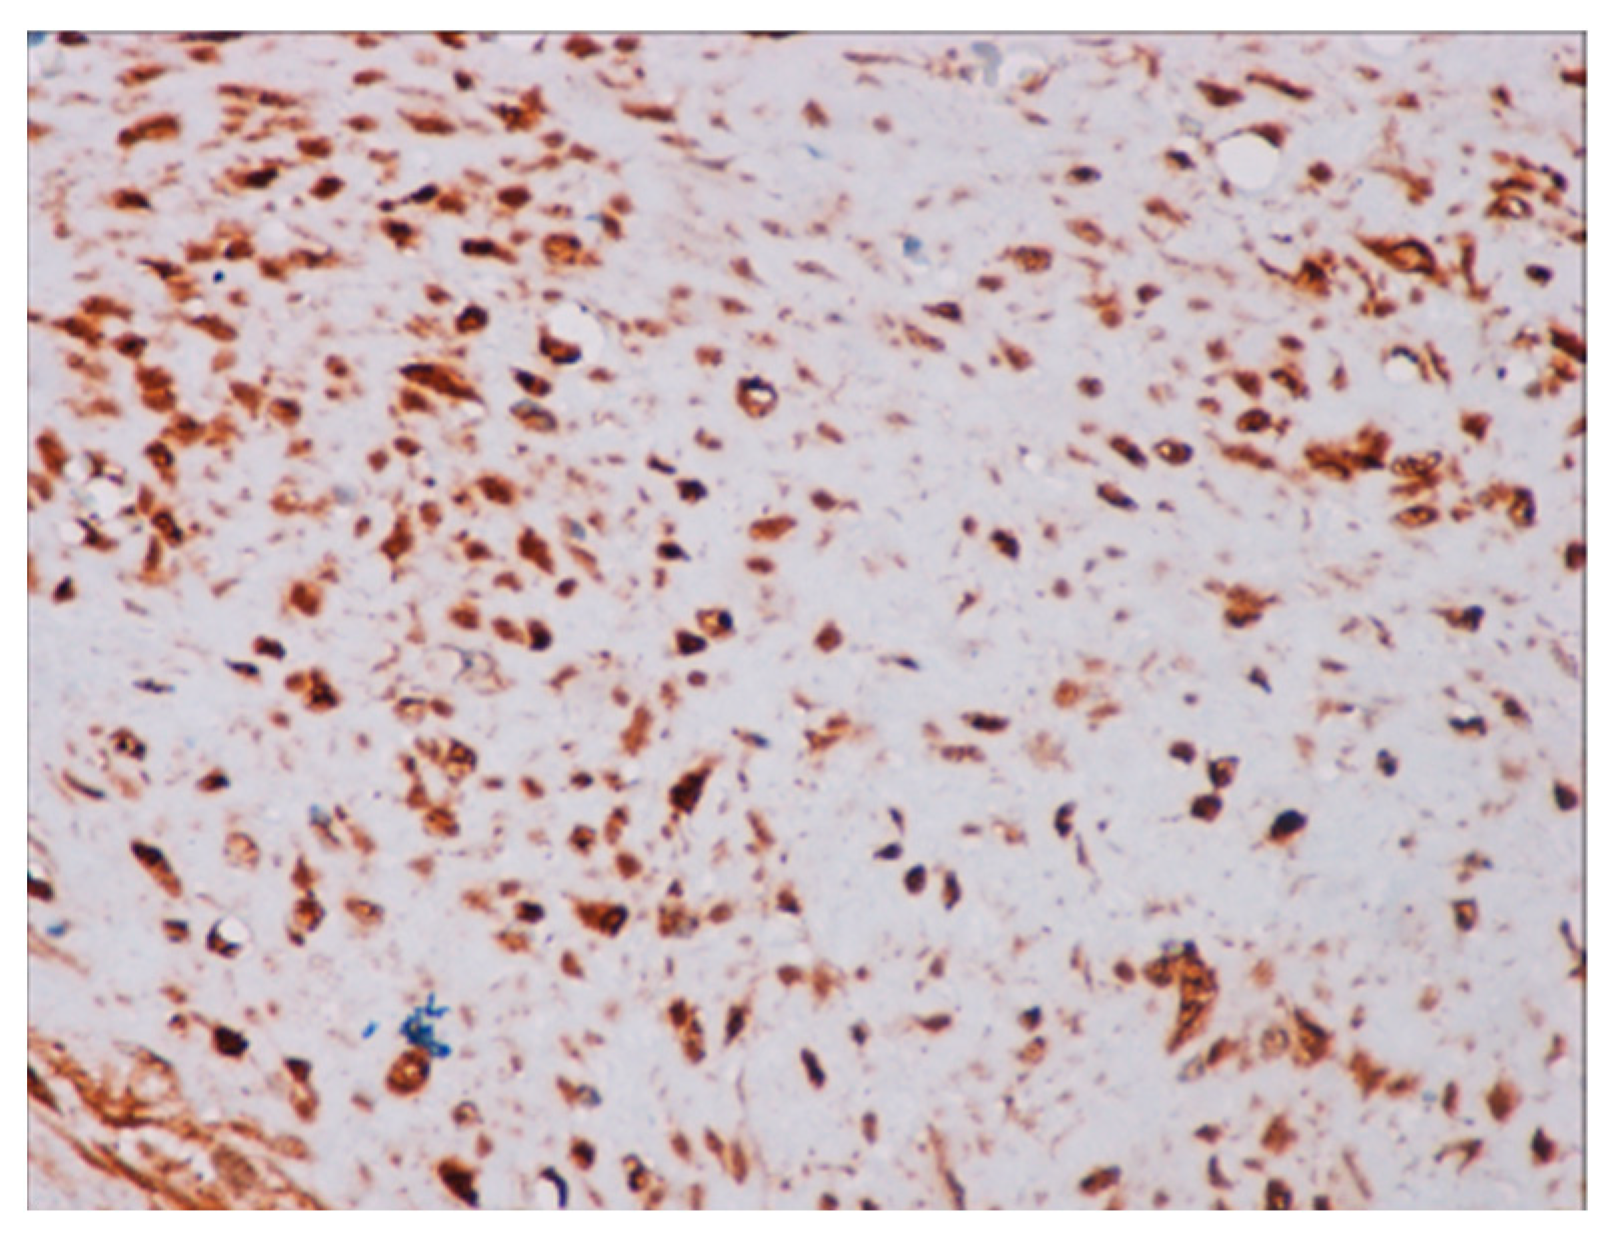

4.3. Histopathological Diagnosis

4.4. Pathology